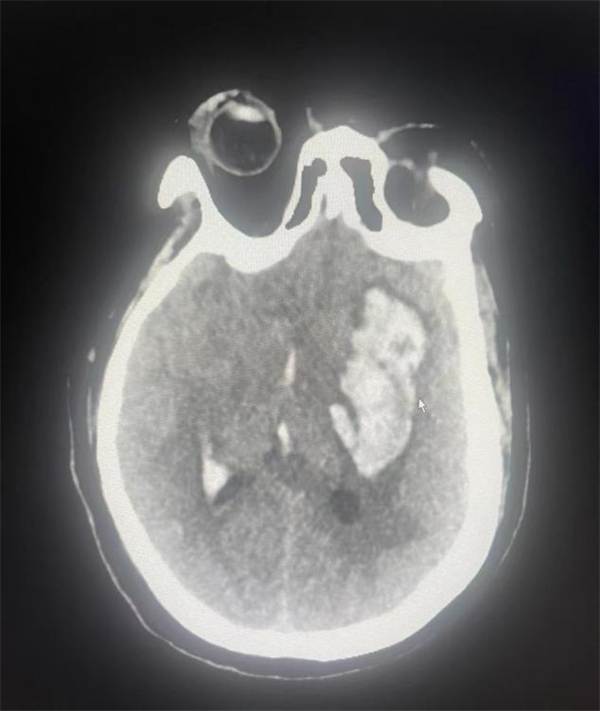

灃東院區(qū)腦病病區(qū)車海江主任醫(yī)師及崔創(chuàng)主治醫(yī)師親自陪同穆阿姨前往放射科完善頭顱影像學(xué)檢查。頭顱CT提示“基底節(jié)出血、繼發(fā)腦室出血、腦疝形成”。結(jié)合穆阿姨的病情,車海江主任及崔創(chuàng)醫(yī)師決定為穆阿姨進(jìn)行手術(shù)。經(jīng)過與家屬充分溝通并征得同意后,決定對穆阿姨實(shí)施“全麻氣管插管下經(jīng)顯微鏡輔助下翼點(diǎn)側(cè)裂島葉入路顱內(nèi)基底節(jié)血腫清除+去骨瓣減壓手術(shù)”。

整個手術(shù)過程非常順利,術(shù)后穆阿姨意識逐漸轉(zhuǎn)為清醒,復(fù)查頭顱CT血腫已經(jīng)完全清除。

手術(shù)前